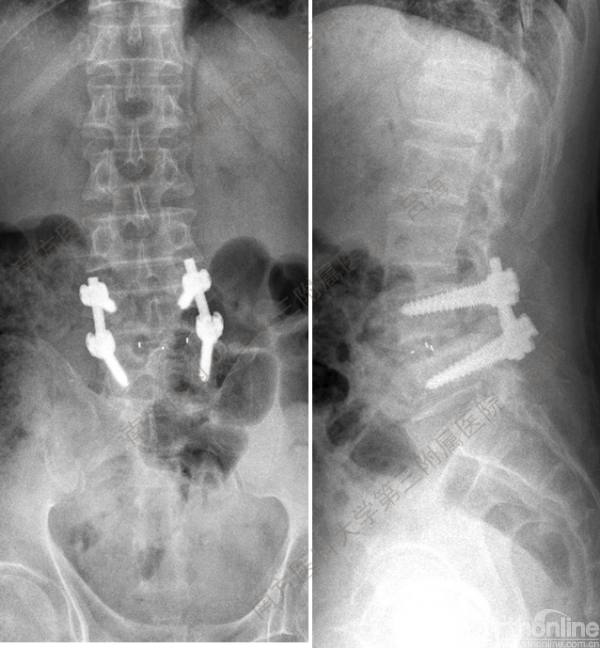

随着社会老龄化进程加快,胸腰椎退行性病变的治疗已经成为脊柱学术界的一个热点话题。MIS-TLIF手术可以治疗多种不同的胸腰椎退行性疾病,南方医科大学第三附属医院吕海教授结合病例为我们一一展示了该术式在治疗不同胸腰椎疾病时的具体手术过程。